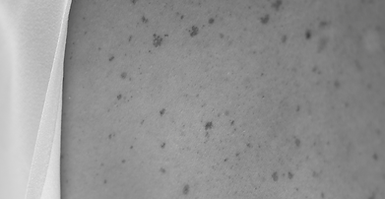

Kožní výrůstky, pigmentové znaménka nebo drobné nerovnosti pleti mohou být nejen estetickým, ale i zdravotním problémem. Na naší klinice je odstraňujeme pomocí moderních laserových technologií, které zajišťují vysokou přesnost, minimální zásah do okolní tkáně a rychlé hojení.

mají pigmentová znaménka, která jsou neestetická, ale nezhoubná